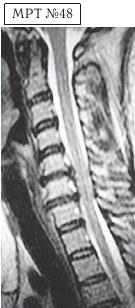

МРТ № 1

На магнитно-резонансной томографии (МРТ) № 1 — шейный отдел позвоночника, в относительно нормальном состоянии.

Шейный отдел позвоночника должен иметь нормально выраженный физиологический лордоз, не должно быть гиполордоза или гиперлордоза, а так же кифотических деформаций.